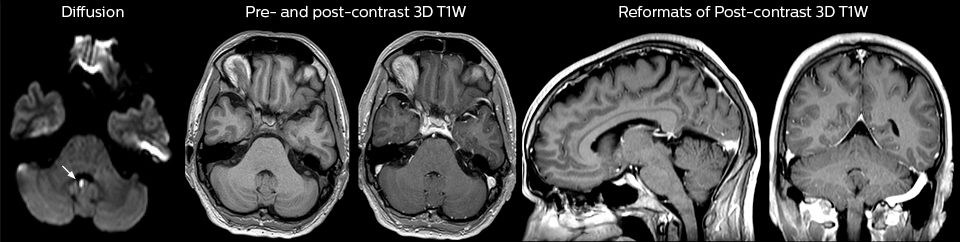

A range of protocol sheets was developed to help ensure that referring physicians order the most appropriate MRI exam. The optimized MRI protocols also include 3D contrast-enhanced imaging, allowing neurosurgeons to comfortably use the isotropic data in the operating room while performing stereotaxic surgery.

“Our results show that a dedicated MRI in the ED can be effectively implemented; patient turnaround times with MRI were on par with CT. Interestingly, even though the MRI exam protocols were shortened, this robust yet rapid scanning still yielded good quality images, further improving our workflow and almost eliminating the need for repeat scans or follow-up scans. So, we’re heading towards first time right imaging,” says Dr. Karis.

At St. Joseph’s Hospital and Medical Center, the dedicated MRI system in the ED has been shown to efficiently provide high quality MR images that assist physicians in making informed decisions on patient diagnoses and take a more definitive decision on follow-up. The decision to have a dedicated ED MRI has resulted in rapid patient turnaround, efficient patient management, and substantial reductions in radiation dose.